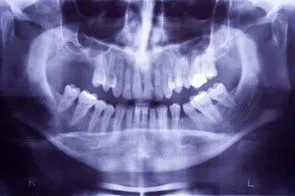

• Panorex

When you lose teeth, and do not replace them, the jawbone deteriorates where the tooth socket once was. This makes it difficult, and in some instances impossible to get dental implants or dentures later on. You may have not had the financial means at the time of the extraction for restorative surgery, but you may have the money now. The good news is that we can perform a process called ridge augmentation to restore the bone structure that is needed for restorative procedures such as dental implants. The process involves lifting the gum from the ridge to expose the defected area of the bone. Then the dentist uses a bone like substance to fill the defected areas. The ridge augmentation greatly improves the appearance of the mouth and increases the chances for success with the implants. With ridge augmentation, your implants will last for years.